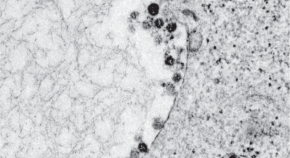

The present outbreak of a coronavirus-associated acute respiratory disease called coronavirus disease 19 (COVID-19) is the third documented spillover of an animal coronavirus to humans in only two decades that has resulted in a major epidemic. The Coronaviridae Study Group (CSG) of the International Committee on Taxonomy of Viruses, which is responsible for developing the classification of viruses and taxon nomenclature of the family Coronaviridae, has assessed the placement of the human pathogen, tentatively named 2019-nCoV, within the Coronaviridae. Based on phylogeny, taxonomy and established practice, the CSG recognizes this virus as forming a sister clade to the prototype human and bat severe acute respiratory syndrome coronaviruses (SARS-CoVs) of the species Severe acute respiratory syndrome-related coronavirus, and designates it as SARS-CoV-2. In order to facilitate communication, the CSG proposes to use the following naming convention for individual isolates: SARS-CoV-2/host/location/isolate/date. While the full spectrum of clinical manifestations associated with SARS-CoV-2 infections in humans remains to be determined, the independent zoonotic transmission of SARS-CoV and SARS-CoV-2 highlights the need for studying viruses at the species level to complement research focused on individual pathogenic viruses of immediate significance. This will improve our understanding of virus–host interactions in an ever-changing environment and enhance our preparedness for future outbreaks.